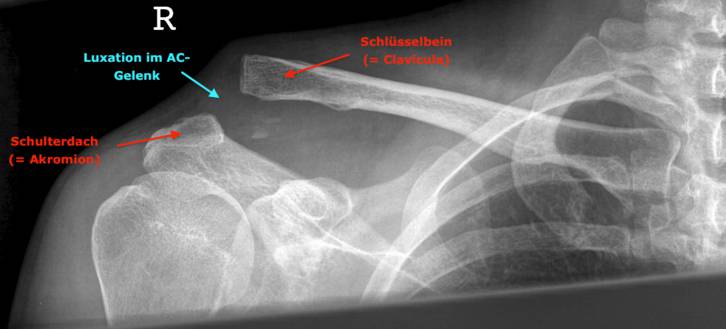

Behandlungen von Schulter-, Ellbogen- und Handgelenks-verletzungen sind oft sehr anspruchsvoll und komplex. Deshalb ist mit einer längeren Erholungsphase in vielen Fällen bis zu 6 Monaten und länger zu rechnen, beispielsweise bei Operationen bei Schulterluxationen und Instabilitäten am Schultergelenk, Schultergelenksarthroskopien bei Einklemmungssyndromen, Rekonstruktion der Rotatorenmanschette, Kunstgelenk-ersatzoperationen an der Schulter. Die Entwicklungen auf diesem Fachgebiet sind enorm vorangeschritten, sodass heute viele Eingriffe in entsprechender arthroskopischer oder minimal-invasiver Technik durchgeführt werden können. Dies führt in der Regel zu bedeutend kürzeren Spitalaufenthalten und schnellerer Erholung.

Die  wichtigsten Verletzungen und Erkrankungen an Schulter, Ellbogen und Hand: